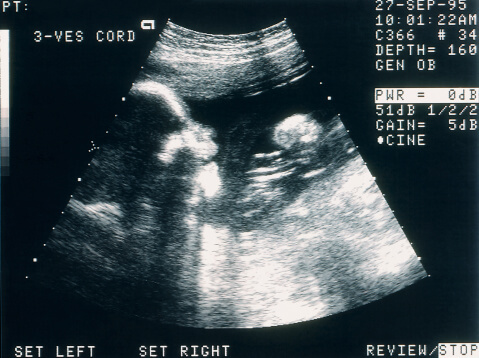

Reading a Sonogram Picture

Reading the sonogram from a prenatal ultrasound is easy if you know what to look for. For example, black areas generally indicate fluid, such as amniotic fluid or blood. Bright white areas indicate solid structures such as bone. In between would be shades of gray that would represent organ structures. With that in mind, identifying things like the baby’s head or legs can help you get oriented.